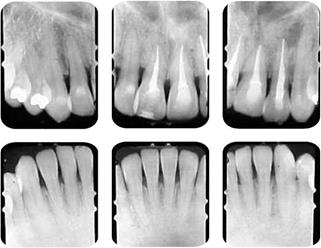

Bolsas periodontales sin sangrado de 4 a 6 mm en el segmento anterior superior e inferior con pérdida de cresta ósea (Cuadro I y figura 3).

Figura 3 Radiografías periapicales que muestran el pobre nivel de cresta alveolar en los incisivos superiores e inferiores.